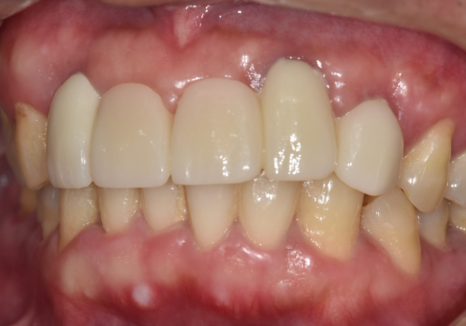

덕분에 치열이 한층 가지런해진 것은 물론이고

이전보다 입매가 안쪽으로 들어가 보여

전체적인 인상 자체가

훨씬 부드럽게 개선되었습니다.

기능적인 회복은 물론 심미적인 부분까지

자연스럽게 마무리되어,

환자분도 저도 많이 만족했던 케이스였네요^^